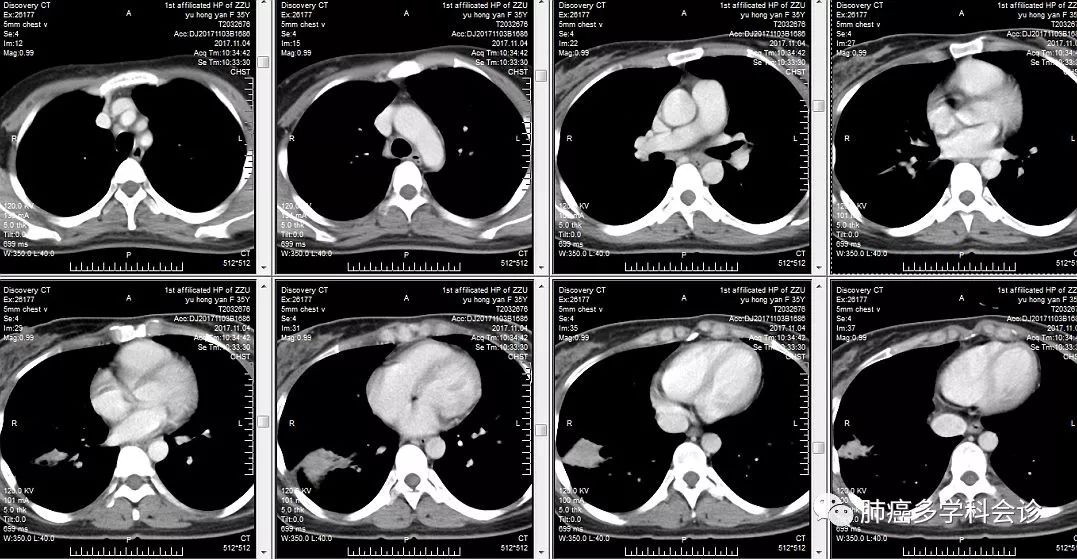

患者余HY,女,35岁。间断胸痛3月余,咳嗽咳白色粘痰,低热。当地CT:双肺下叶炎症,右下肺斑片状密度影较前扩大。支气管镜未见明显异常。

入院后胸部CT如下: